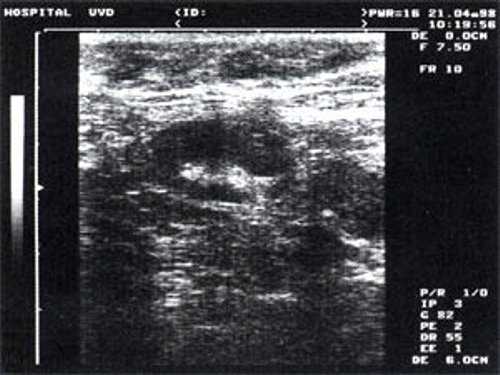

Практически во всех случаях дифференцировали лимфатический узел Кютнера (югулодигастральный), расположенный на границе средней и верхней трети шеи. Выявляемые лимфатические узлы имели размеры от 0,5 х 0,2 см до 2,3 х 0,8 см. УЗ-оценку производили после полипозиционного осмотра и нахождения самой длинной горизонтальной оси, что и принимали за максимальный поперечный диаметр. Большая часть лимфатических узлов (187) имели овальную форму с соотношением поперечного/переднезаднего более 1 (рис. 1 - 3). Тенденцию к округлению имели 30 лимфатических узлов, соотношение поперечного/переднезаднего приближалось к 1.

Мы установили, что, как правило, более округлая конфигурация лимфатического узла при его размерах, превышавших 10 мм, сопровождалась небольшими болевыми ощущениями, и более выраженной простудной (воспалительного характера) симптоматикой. Лимфатические узлы менее 10 мм чаще всего плохо пальпировались, либо вообще не выявлялись пальпаторно. Во всех случаях эхографически хорошо дифференцировался гипоэхогенный кортикальный слой и широкое, средней или чуть ниже средней эхогенности изображение области ворот лимфатических узлов. Четкость дифференциации составных частей лимфатического узла была снижена при размерах менее 5 мм. Мы отмечали различную толщину гипоэхогенного изображения области коры лимфатического узла: от очень широкой - при выраженности или прогрессировании воспалительного процесса, до узкой - на фоне положительной динамики.

Мы выявили совершенно другую УЗ-картину состояния пальпируемых лимфатических узлов при динамической оценке у больных с синдромом иммунодефицита. Оцениваемые лимфатические узлы имели эхографические признаки доброкачественного процесса, в большинстве наблюдений их размеры превышали 2-2,5 см. При этом во всех случаях дифференцировались составные части лимфатического узла. Определялся узкий кортикальный слой и широкая гиперэхогенная сердцевина при сохранении овальной конфигурации и соотношении поперечного/переднезаднего более 1.

При повторных УЗ осмотрах на фоне массированной противовоспатительной терапии было отмечено увеличение числа лимфатических узлов вовлеченных в процесс активизации. При этом заметной перестройки эхоструктуры и уменьшения размеров в наблюдаемых лимфатических узлах отмечено не было (рис 4).

Рис. 4. Варианты изображения увеличенного лимфатического узла с УЗ-признаками доброкачественной аденопатии у больного с синдромом иммунодефицита.